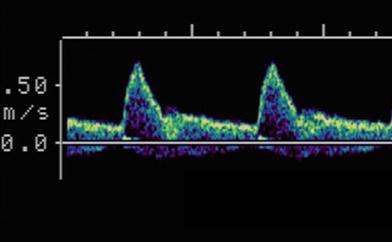

Explain the waveform of the ICA

low resistant - constant forward flow

Forward flow throughout the cardiac cycle